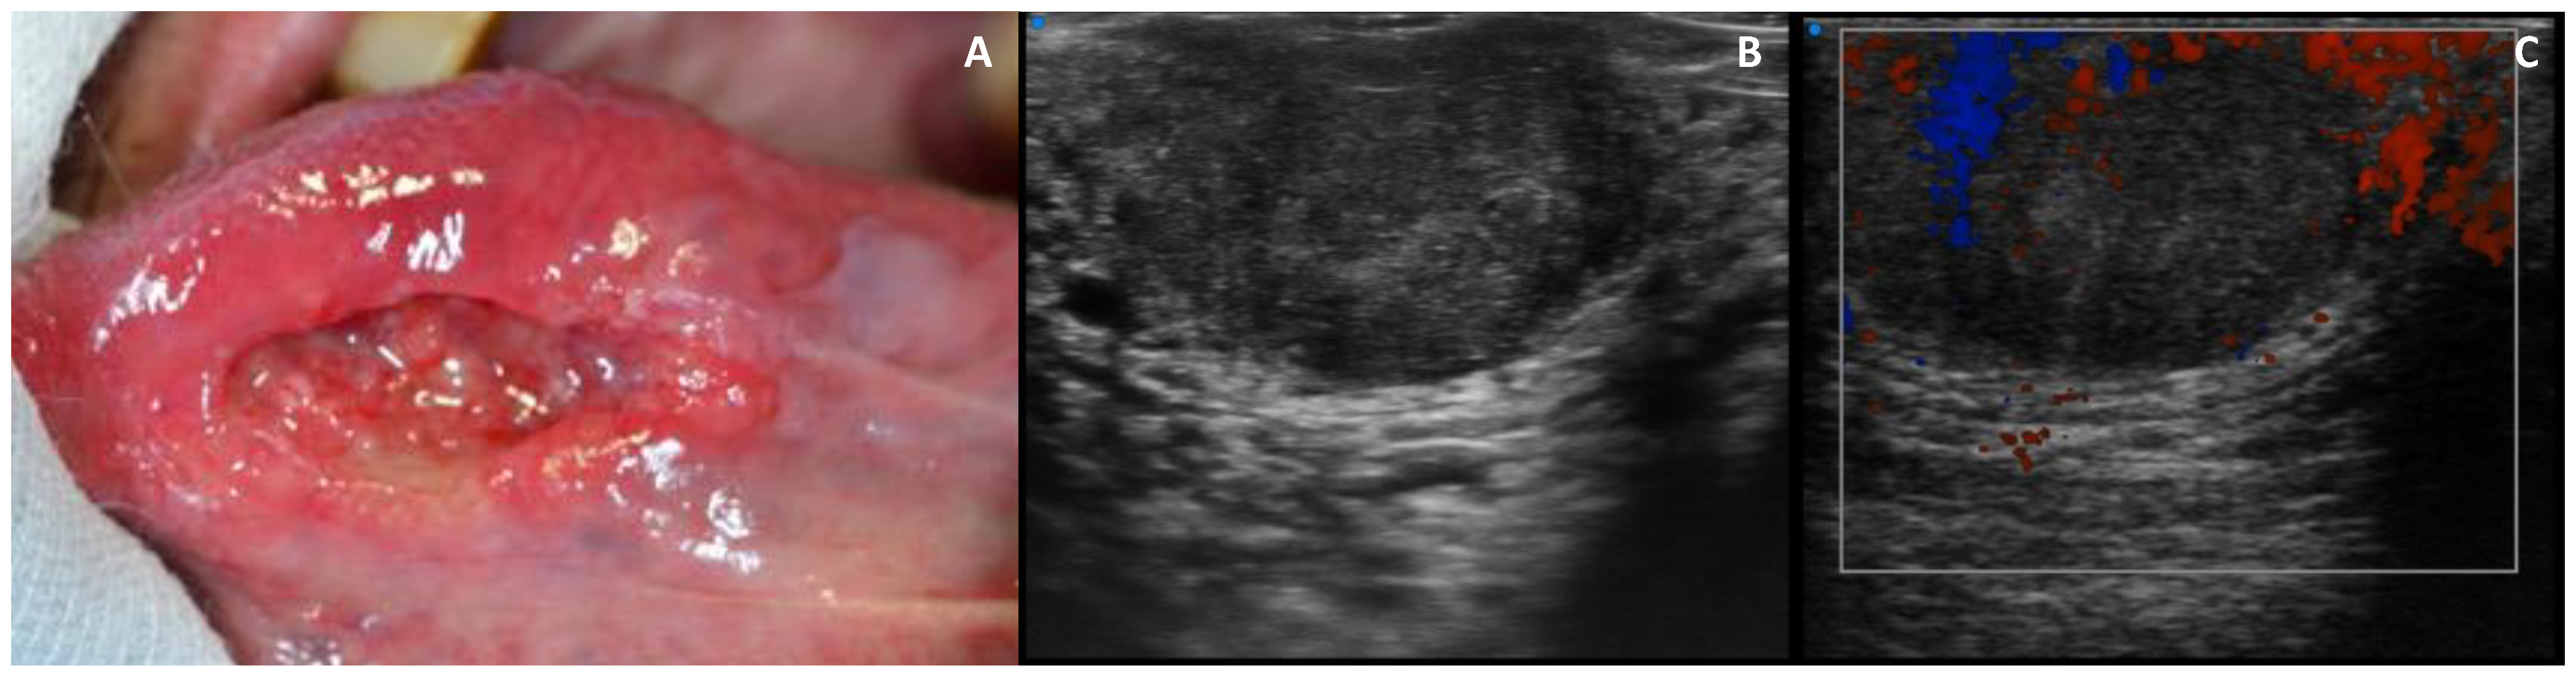

3.4. Echogenicity

3.5. Vascularization